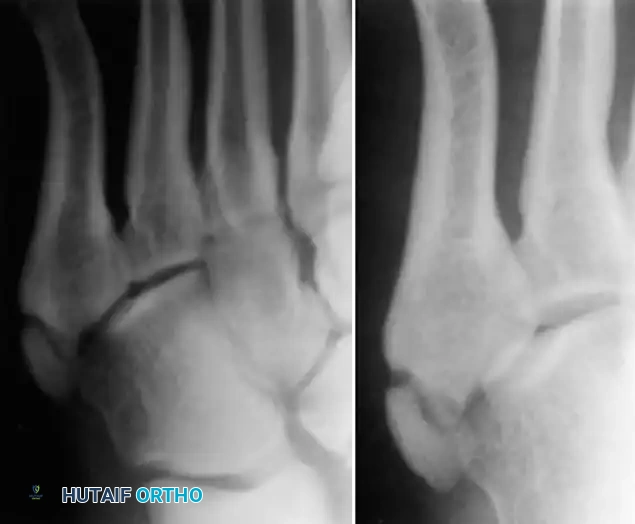

Early radiographic signs include joint space widening and subtle sclerosis of the metatarsal head. As the disease progresses, the subchondral bone collapses, leading to flattening of the articular surface, fragmentation, and the formation of loose bodies.

Condensation and sclerosis in the third metatarsal compared with the second and fourth metatarsals, indicating early acute Freiberg disease. Bone scan shows increased uptake in the metatarsal head.

Advanced stages are characterized by severe joint destruction, osteophyte formation, and intra-articular loose bodies that mechanically block joint motion.

Freiberg infraction of the second metatarsal with distinct intra-articular loose bodies.

Advanced degenerative changes and flattening of the metatarsal head in late-stage Freiberg infraction.